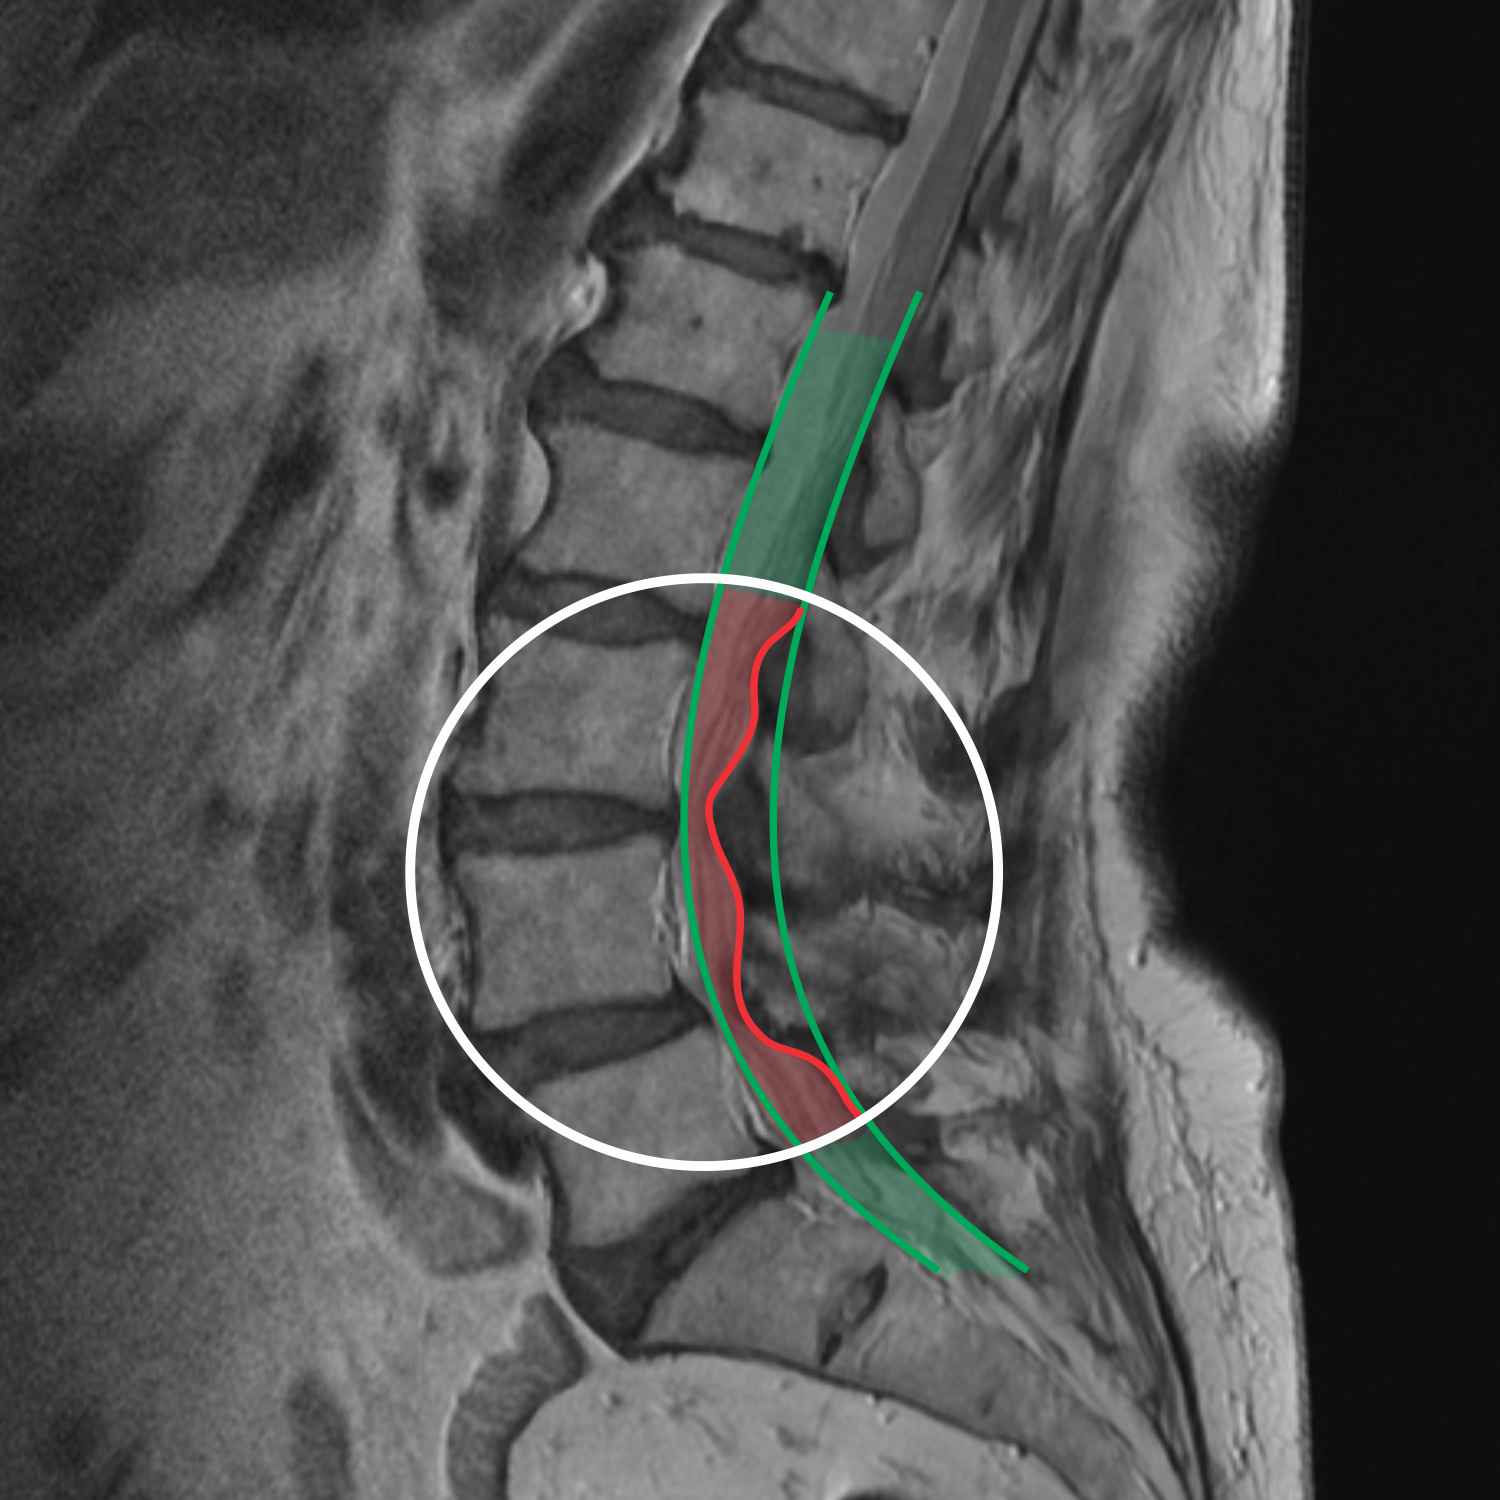

Spondilolisteza

Spondilolisteza je stanje hrbtenice, pri katerem eno vretence zdrsne naprej pred vretence pod njim. Zakaj pride do te spremembe?

Spondilolisteza je tretja najbolj pogosta zadeva, ki se pojavlja predvsem pri ženskah zaradi povečane lordoze, hormonskih sprememb in posledično mehkejšega tkiva. Pri tem se eno vretence premakne naprej, s tem se zamakne tudi disk, ki se lahko mimogrede dotakne še kakšnega živca ali hrbtenjače.

Z leti hrbtenica ni več tako stabilna. Spondilolisteza je videti kot stolpec iz kock, ki ima eno kocko malce zamaknjeno. Stabilnost stolpca se zmanjša in ob večji kompresiji lahko pride do bolečine, saj en delček ni več svojem mestu.

To sicer lahko uravnavamo s pravilnim gibanjem in stabilizacijami, vendar se vretenca ne da več postaviti nazaj. V kritičnih situacijah je nujna operacija. V ambulanti s stabilizacijskimi mišicami imobiliziramo ta del, in ker ga stisnemo, se sila prenese na mišice in ne na vretenca. Zato oseba lahko opravi prej problematičen gib, kar je z vidika normalnega življenja zelo pomembno.